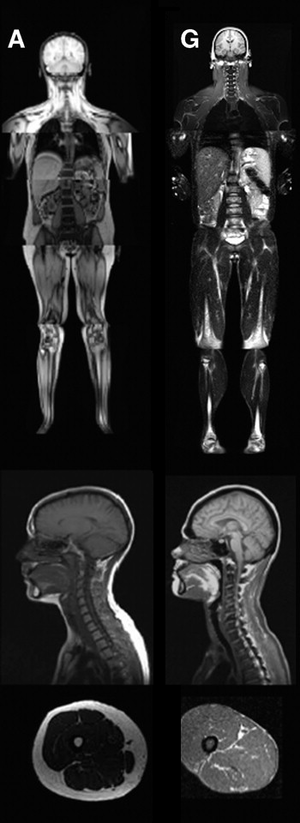

| An MRI image illustrating the lack of subcutaneous fat of a patient with the disease (G) compared to a control patient (A). | |